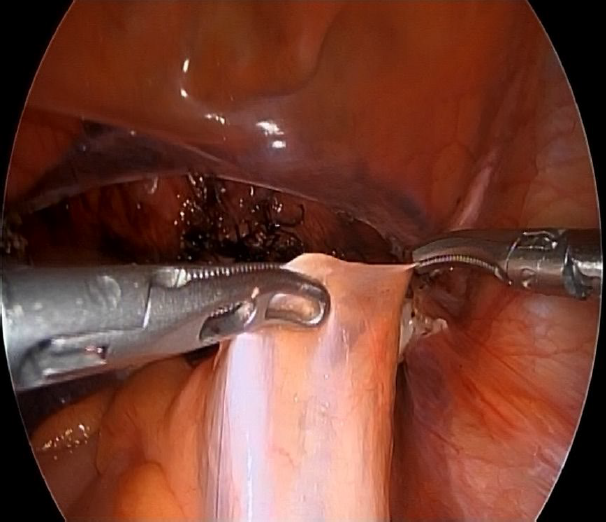

Two lateral 5 mm trocar and one 10 mm suprapubic trocar were needed in all of the procedures. Once the hysterectomy concluded, the patient remained in Lloyd-Davis position, the promontorium was located, and the surgeon managed to arrange the colon to the left in order to get a direct visión of the peritoneum. To administer the medication, two Croce Olmi forceps were used to grasp the peritoneum and tent it up (Figure 1), this way a laparoscopic needle was introduced through the central trocar loaded with ropivacaine 20 mL (0.2%) (Figure 2) and the anesthetic was infiltrated in the retroperitoneal space with the help of the forceps (Figure 3-4). After the withdrawal of the laparoscopic needle from the retroperitoneal space, the Croce Olmi forceps were used to keep the retroperitoneum tented and allow the anesthetic to properly infiltrate the retroperitoneal space (Figure 5). This procedure was performed under direct laparoscopic vision at the end of the surgical procedure, right before the withdrawal of the laparoscopic instruments. This was done with the intention of not letting the surgical time be a biased element that may vary from patient to patient, decreasing the anesthetic effect during the post-surgical period. The anesthetic was successfully administered in all of the patients in the SHP group. There were no immediate complications reported in any of the procedures. Table 1. Medications and doses used to induce general anesthesia and additional medications administered by the anesthesiology team.

Figure 2. Introduction of a laparoscopic needle into the abdominal cavity to administer the anesthetic.